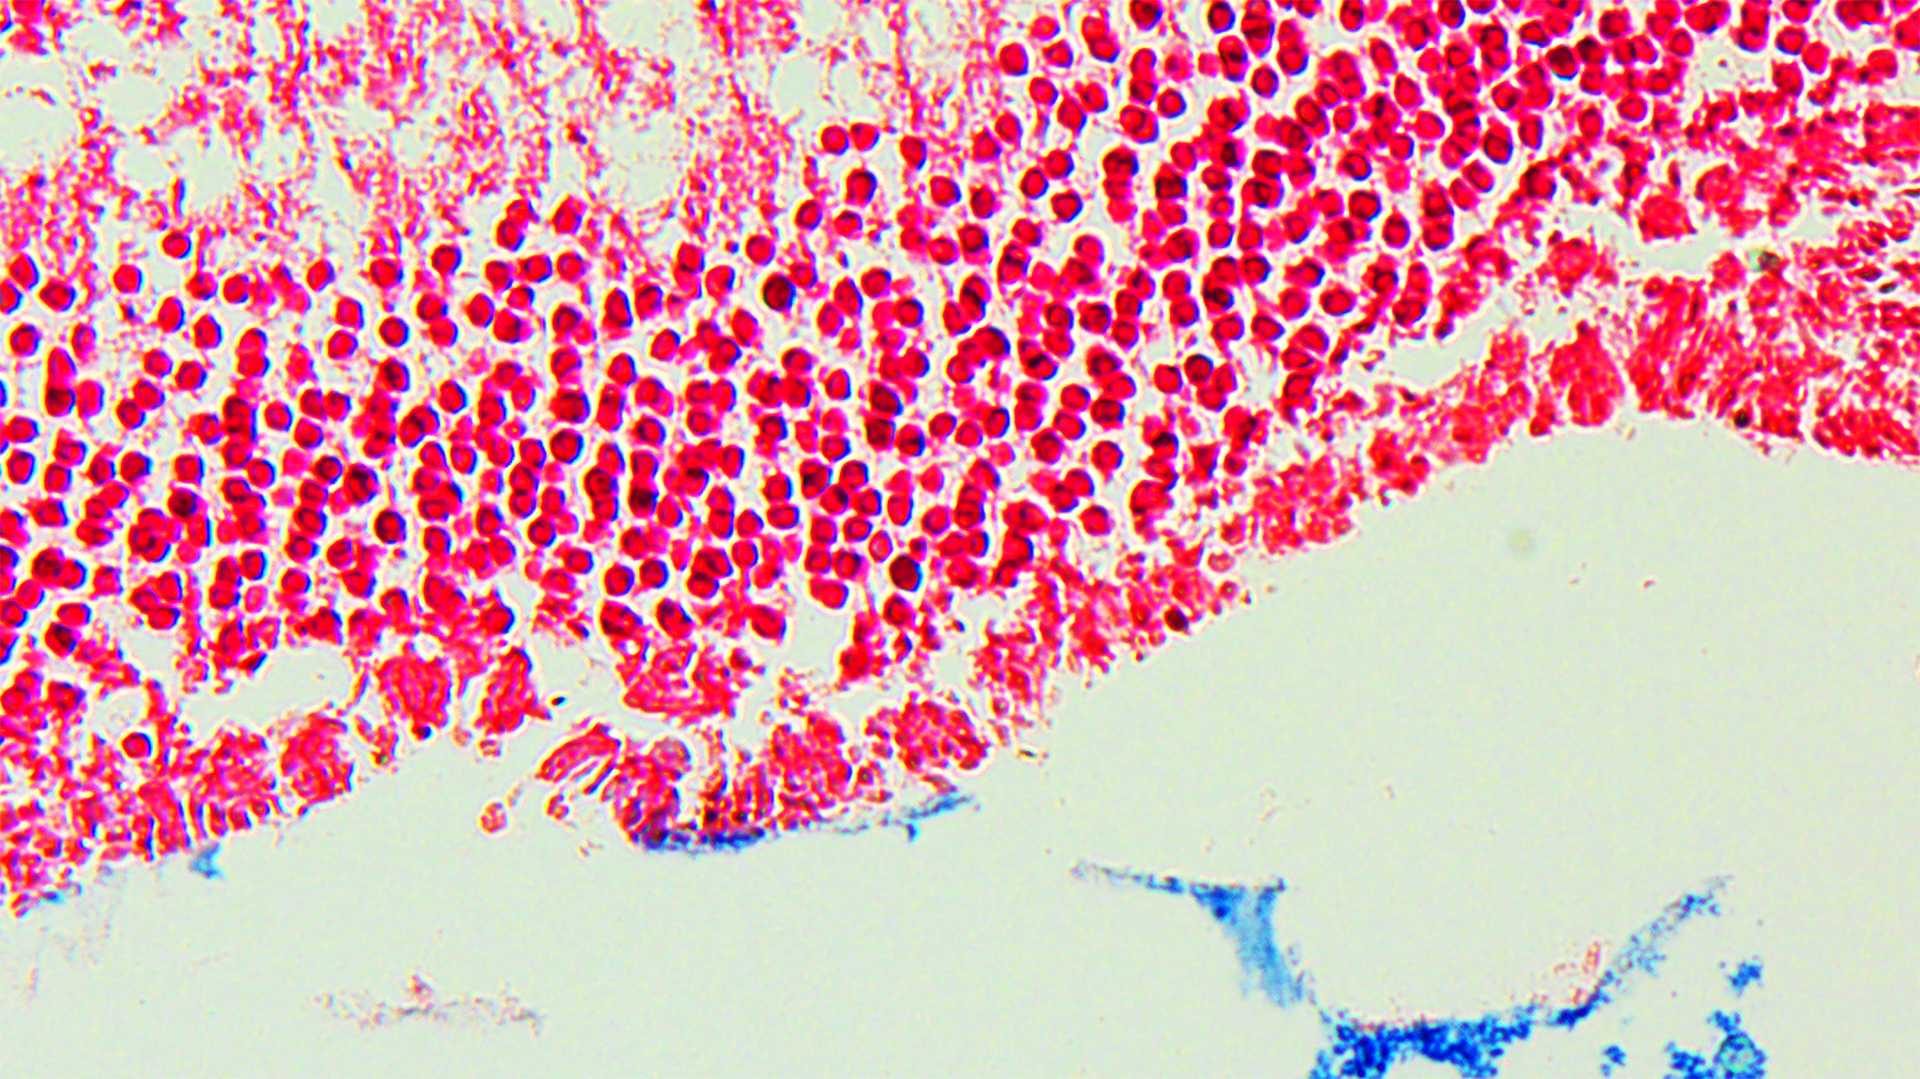

The researchers then induced oxidative stress in the Brca2 mutant rats by administering ferric nitrilotriacetate (Fe-NTA) to their renal tubules. They used Fe-NTA, a form of iron, in this experiment, because oxidative stress caused by iron overload is reported to be highly associated with cancer development. However, no differences were found in tumor incidence, progression speed or malignancy grade between wild-type and Brca2-mutant rats. Then, they investigated why iron-dependent oxidative stress canceled the cancer-promoting effect of the BRCA2mutation.

One week after the administration of Fe-NTA, the rats’ tubular cells exhibited an increase in antioxidant activity. Consequently, lipid peroxidation was inhibited, and resistance to ferroptosis—a type of cell death dependent on iron—was observed.

However, three weeks after starting Fe-NTA administration, the researchers observed the opposite effect. In the Brca2 mutant rats, the accumulation of catalytic iron damaged mitochondria and led to an increase in lipid peroxidation. As a result, ferroptosis was activated, which surprisingly contributed to the elimination of cells with the potential to become cancerous. These results suggest that ferroptosis counteracted the genomic instability caused by BRCA2 deficiency, acting instead as a tumor suppressor.

Top image: How BRCA2-deficiency acts on Fe-NTA induced renal carcinogenesis (Credit: Shinya Toyokuni)